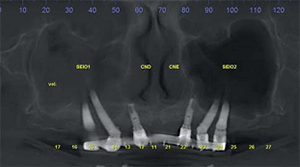

Aspergiloma é uma formação fúngica que ocorre em cavidades do sistema respiratório e pode estar associado a tratamentos odontológicos. Paciente do sexo feminino apresentou sinusite crônica persistente não responsiva a farmacoterapia após fixação de quatro implantes zigomáticos.

Após exame de tomografia computadorizada verificou-se possível comunicação bucossinusal mantida por um dos implantes e imagem sugestiva de aspergiloma.

O presente artigo demonstra os passos para remoção dos implantes infectados e do aspergiloma. Também é apresentada uma discussão sobre as características dos aspergilomas de seio maxilar e os fatores que predispõem a sua formação em tratamentos odontológicos, especialmente com implantes zigomáticos.